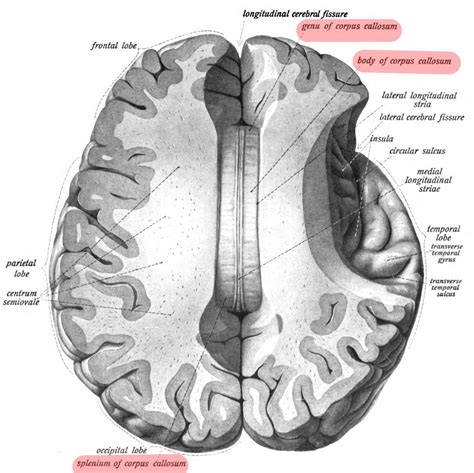

The corpus callosum is divided into four distinct regions, moving from anterior to posterior: the rostrum, the genu, the body (or trunk), and finally, the splenium. As the most posterior and thickest part of the entire structure, the splenium of corpus callosum plays a disproportionately large role in brain function. It acts as a bridge that enables the left and right hemispheres to synchronize their activity, ensuring that the brain operates as a unified whole rather than two separate processing units.

The fibers passing through the splenium are predominantly responsible for connecting the temporal, parietal, and occipital lobes. This anatomical arrangement is crucial because these lobes are heavily involved in sensory perception. By facilitating communication between these areas, the splenium ensures that visual input—processed primarily in the occipital lobes—is integrated seamlessly with auditory information and complex sensory data from the parietal lobes.

• Size: It is the largest, most rounded part of the corpus callosum.